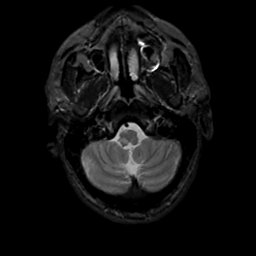

MR Study #10, April 28, 1991 -- Slice #6